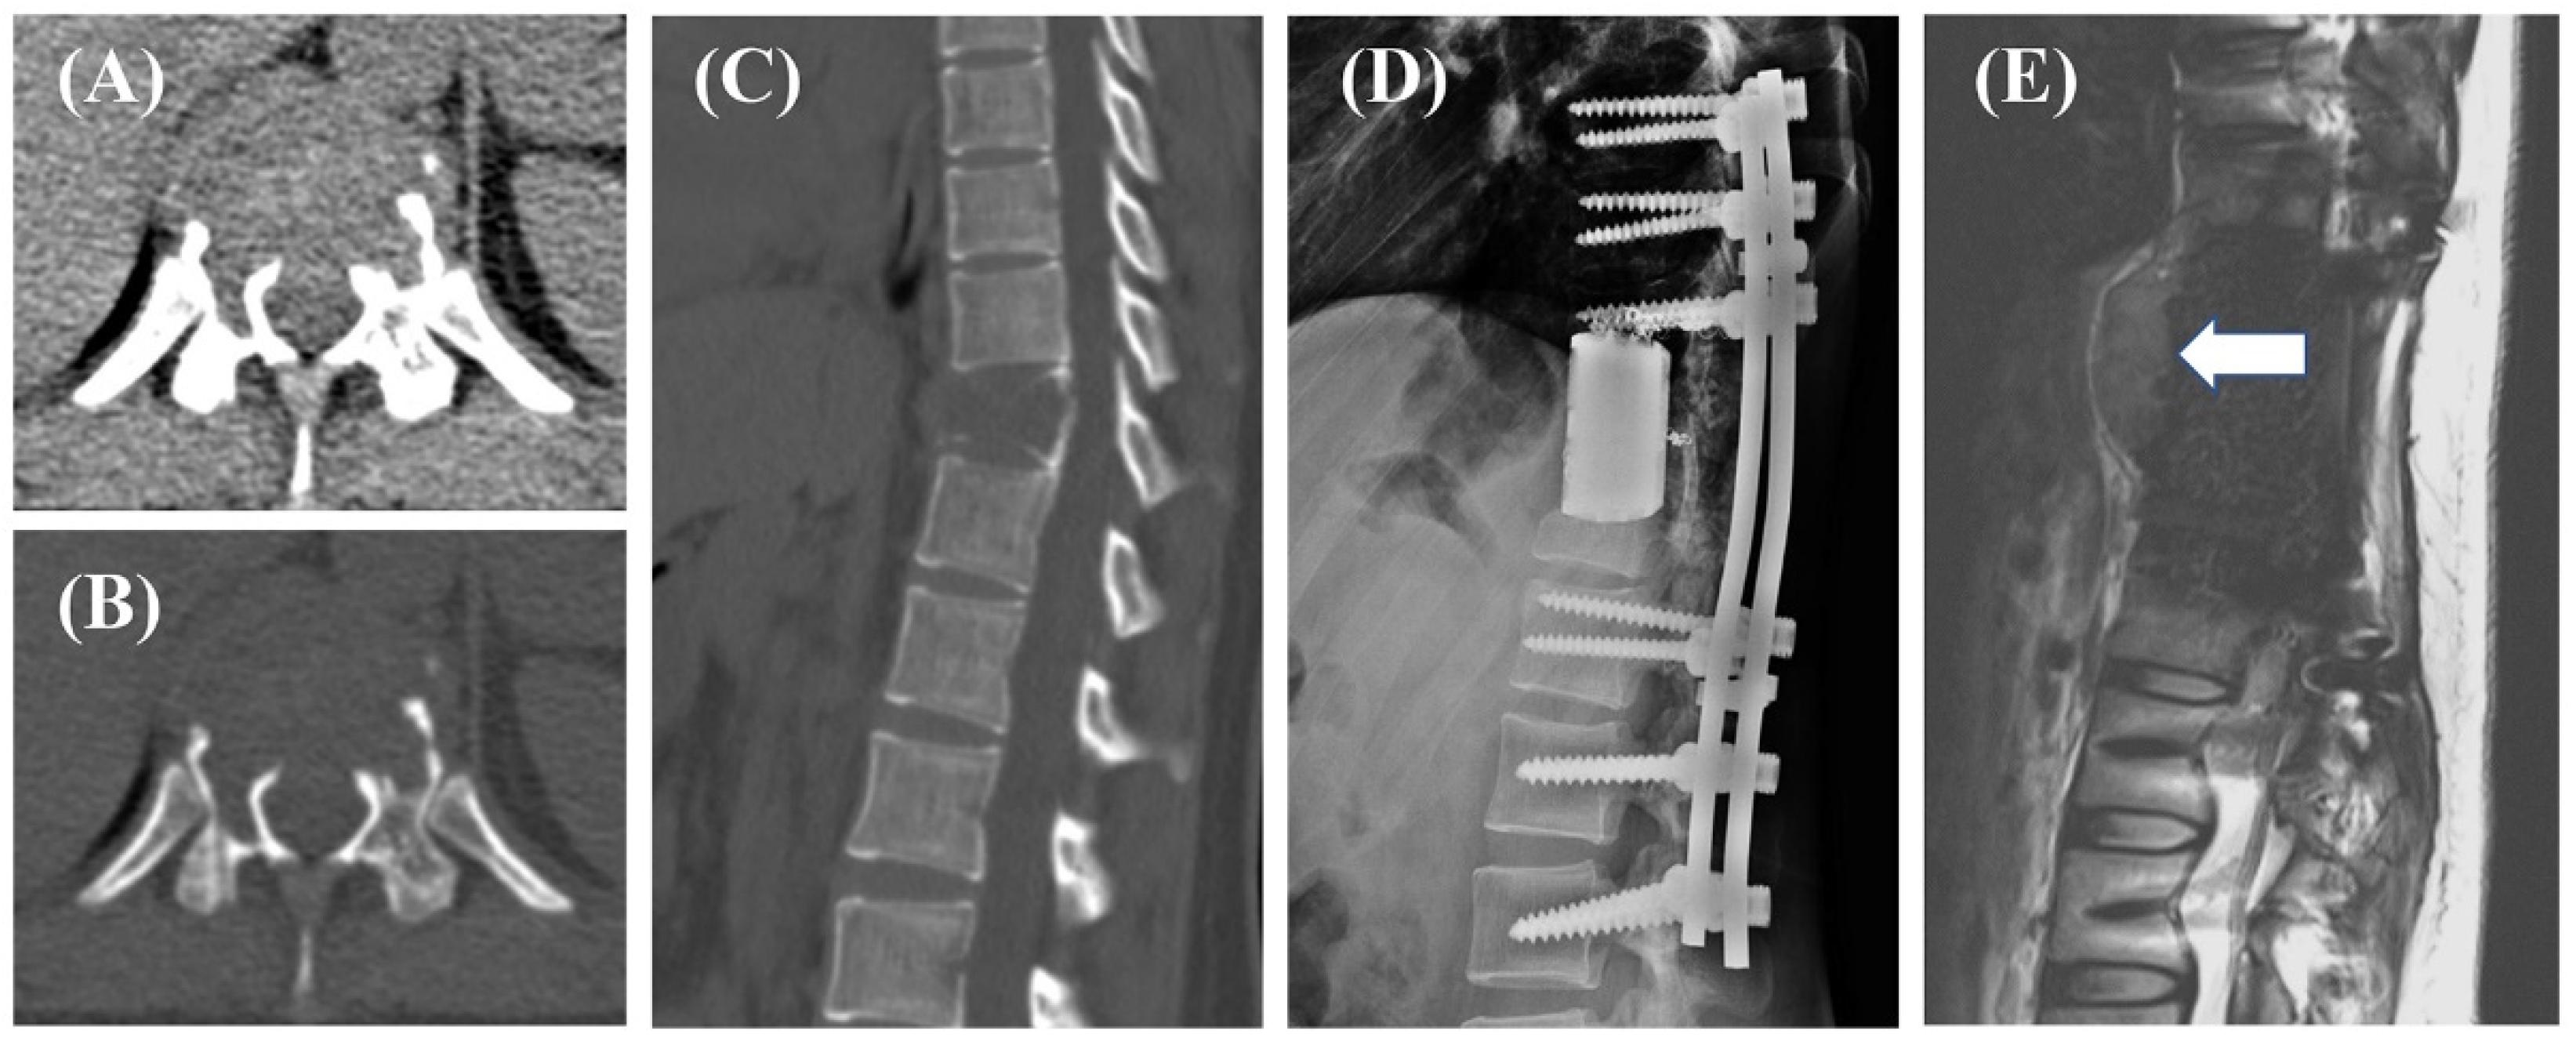

Based on previous studies, surgery and preoperative radiotherapy may have an impact on postoperative recurrence, so we included 75 patients who underwent total en bloc spondylectomy (TES) without preoperative radiotherapy for survival analysis to evaluate the prognostic significance of RANKL levels. Two cases were shown in Figure 2 and Figure 3.

Figure 2.

A 29-year-old female, axial (A,B) and sagittal (C) CT images showed the bone destruction of the T12, managed with total en bloc spondylectomy (TES, (D)). Postoperative pathology suggested a high expression of RANKL in the tumor. The patient did not undergo radiotherapy. At a 10-month follow-up review, recurrence was detected ((E), arrow).

Treatment of GCTB cases located in the spine is challenging, as en bloc or wide resection is technically difficult and recurrence is common [6]. Improving the prognosis of GCTB of the spine is the focus of surgeons today. Considering the risks faced by patients undergoing the procedure, accurate preoperative stratification of patient prognosis can help in treatment plan planning and precise treatment. Using bioinformatics and combinatorial screening approaches to determine biomarker expression status could be useful in identifying patients who may benefit most from treatment. The RANK/RANKL pathway is often overexpressed and has been positively correlated with tumor progression and advanced disease in primary malignant tumors of the bone, including osteosarcoma, multiple myeloma, and GCTB [16,17,18,19,20]. Moreover, RANK and RANKL expressions are often higher in malignant histological subtypes of bone cancer. For example, RANKL expression is often elevated in Stage III GCTB, and is a useful prognostic marker for predicting the risk of local disease recurrence [21]. Additionally, elevated RANK and RANKL may significantly increase the risk of metastasis [3]. In this study, we reveal for the first time that RANKL expression status is significantly correlated with disease prognosis in patients with spinal GCTB in a clinical cohort. This highlights that drugs targeting the RANK/RANKL pathway may effectively improve patient outcomes beyond merely inhibiting bone tissue destruction. Patients with recurrence with high RANKL expression, as in Figure 2, may be able to improve their prognosis if they are evaluated correctly early preoperatively, are able to suggest drug availability, surgeons expand resection, and postoperative radiation therapy.